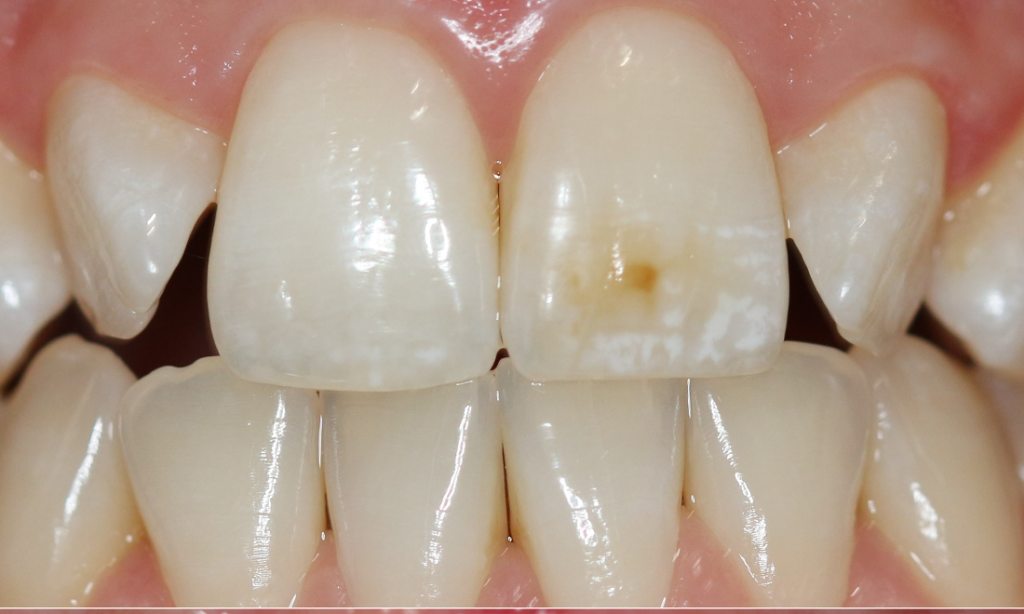

Quando si parla di igiene orale quotidiana, la maggior parte delle persone pensa subito allo spazzolino e al dentifricio. In realtà, per mantenere davvero sani denti e gengive, esiste un alleato fondamentale che spesso viene sottovalutato: il filo interdentale. Perché lo spazzolino da solo non basta Lo spazzolino è essenziale per rimuovere la placca batterica dalle…